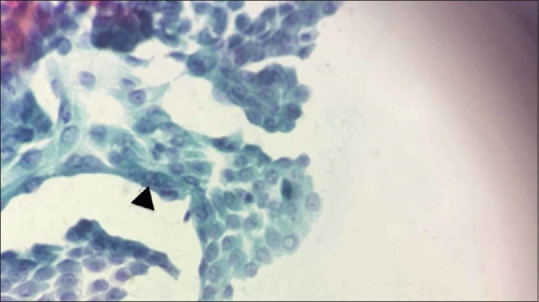

Background: Aspiration cytology is one of the first-line diagnostic tests in thyroid malignancies. Fine-needle aspiration cytology (FNAC) in thyroid lesions causes hemorrhagic smear and cell trauma, often leading to the repetition of smear and delay in diagnosis. This study was conducted to identify the diagnostically superior technique with regard to thyroid swelling and to assess the quality of smears obtained from FNAC and fine-needle nonaspiration cytology (FNNAC).

Methodology: This was a prospective diagnostic study carried out for 2 years in a tertiary care center from South India. All patients with complaints of thyroid swellings, after examination, underwent FNNAC, followed by FNAC of the lesion. They underwent thyroidectomy when indicated. The final postoperative biopsy reports were compared with the preoperative reports of these two techniques (FNNAC and FNAC). The quality of smears was compared using Mair's score.

Results: The sensitivity, specificity, positive predictive value, negative predictive value, and accuracy in diagnosing malignancy were 93.4%, 100%, 100%, 98.78%, and 98.96% for FNNAC and 94.12%, 100%, 100%, 98.82%, and 99% for FNAC, respectively, which were comparable. Regarding the quality of smears, FNNAC had more smears with less blood in the background. FNAC had more smears with adequate cellularity. The difference in overall Mair's score between the two techniques was not significant (P = 0.28).

Conclusion: No difference was found in the accuracy of FNAC and FNNAC in diagnosing thyroid lesions. Furthermore, the smear quality of both techniques was comparable. Hence, either can be used based on the operator's preference and experience.